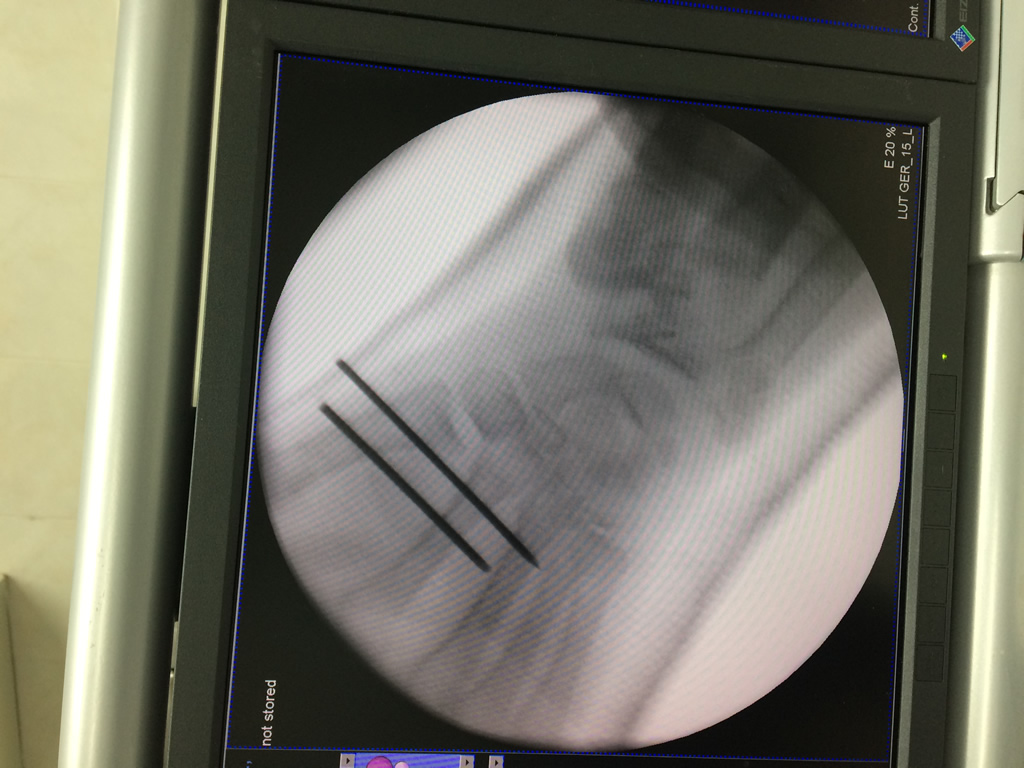

Cirugías de Muñecas

Los procedimientos más comunes en cirugía de la mano son aquellos destinados a reparar traumatismos, incluyendo lesiones de tendones, nervios, vasos sanguíneos, y articulaciones; huesos fracturados; y quemaduras, cortes, y otros daños de la piel.